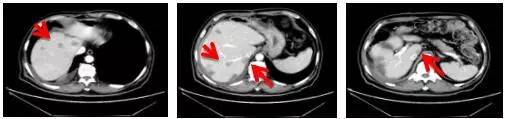

经上述方案治疗6个周期以后,肝脏肿瘤已经明显缩小。经化疗科再次讨论,决定加行肝转移瘤微波消融术,以期尽量消除残存病灶。2015年12月8日,在王潍博主持下,化疗科医生郑爱民副主任医师对该病例肝内病灶成功进行了消融治疗。

患者微波消融手术之后,病灶消融完全

消融前

消融后